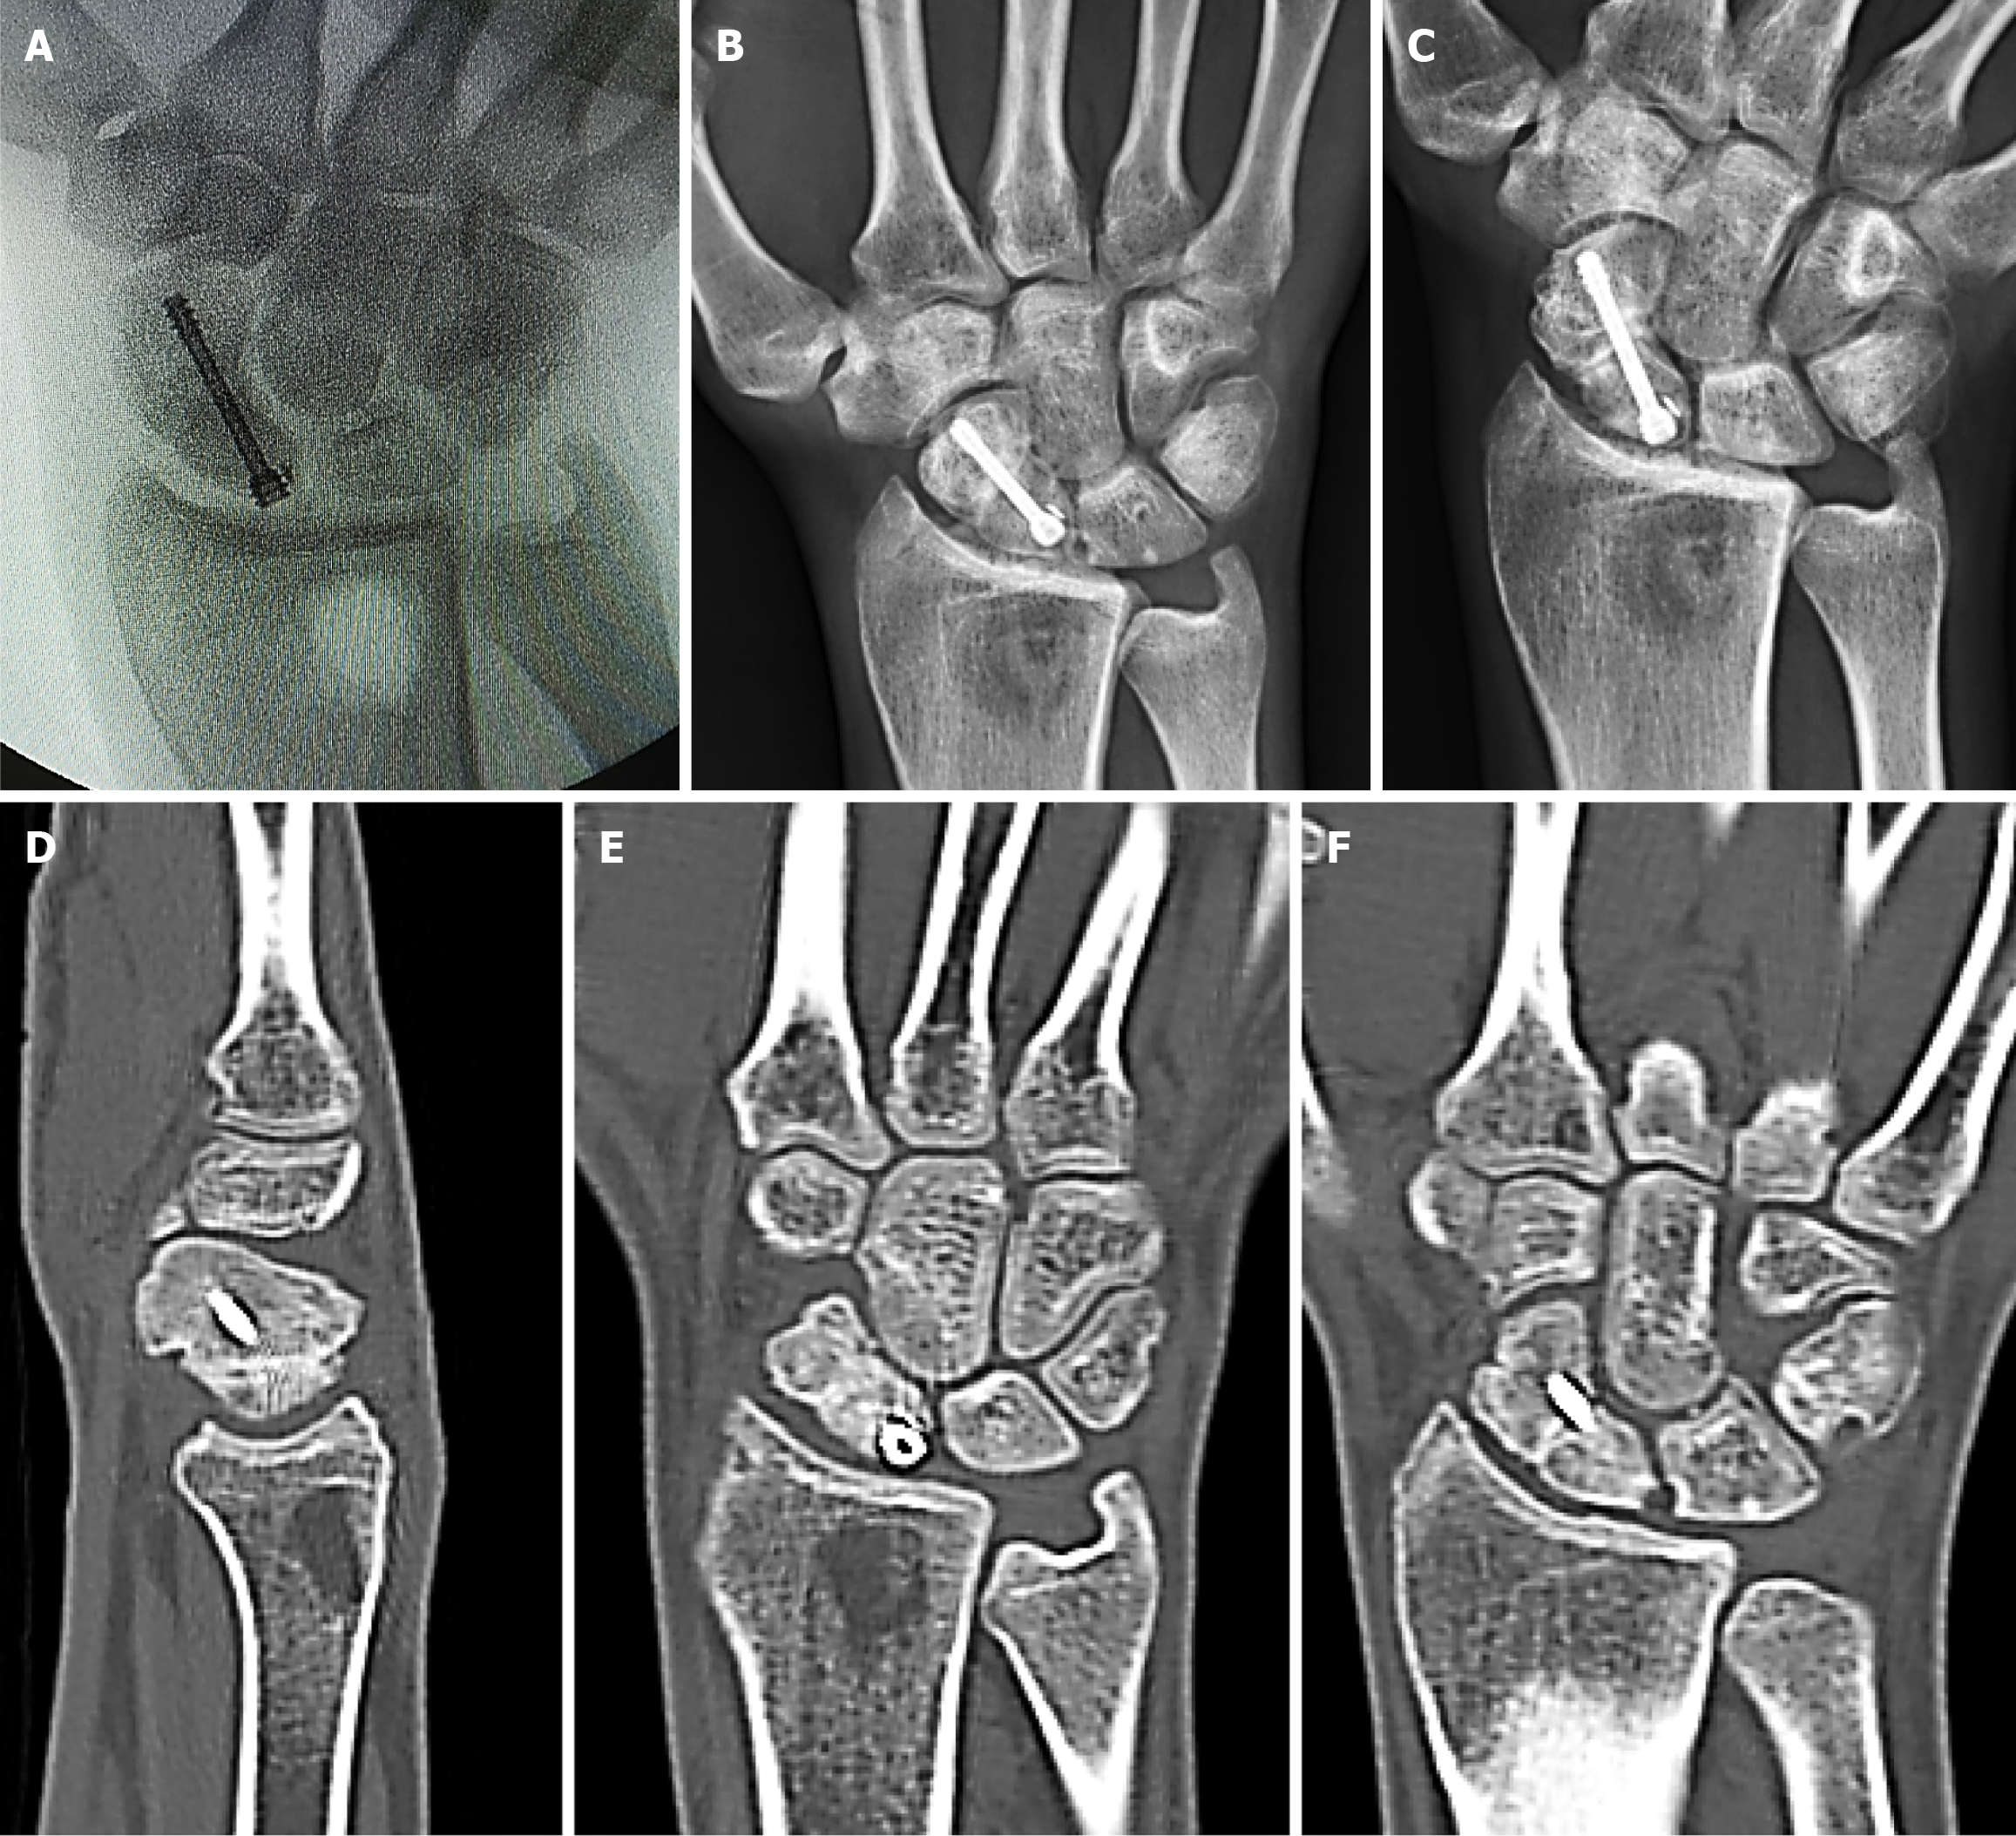

Figure 4 Healing outcome of waist nonunion fixed with cancellous bone grafting.

A: Intraoperative fluoroscopic image showing fixation of a waist nonunion using cancellous bone grafting harvested from the distal radius; a small fragment of a broken drill bit is embedded in the proximal pole; B-F: Postoperative anteroposterior and scaphoid-view radiographs and corresponding sagittal and coronal computed tomography slices at three months, showing complete healing.